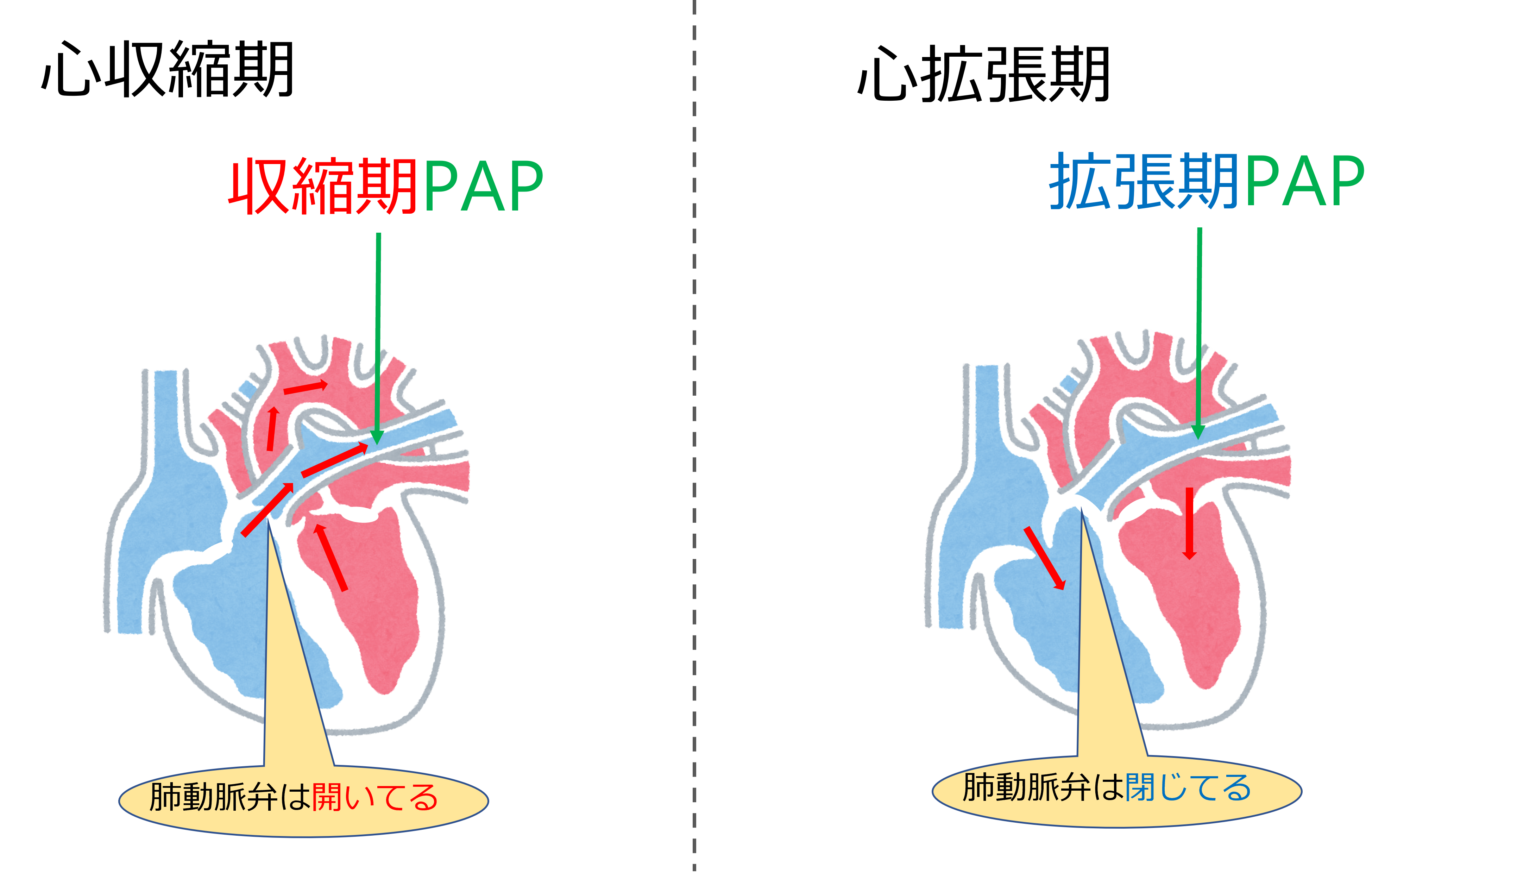

この処置自体は、右心カテーテル法と呼ばれることもあります。これは、心臓の右側を流れる血液の圧力を測定できるためです。 3 つの異なる場所で圧力を測定します。

- 肺動脈

- 次に医師は肺動脈の血圧を測定します。